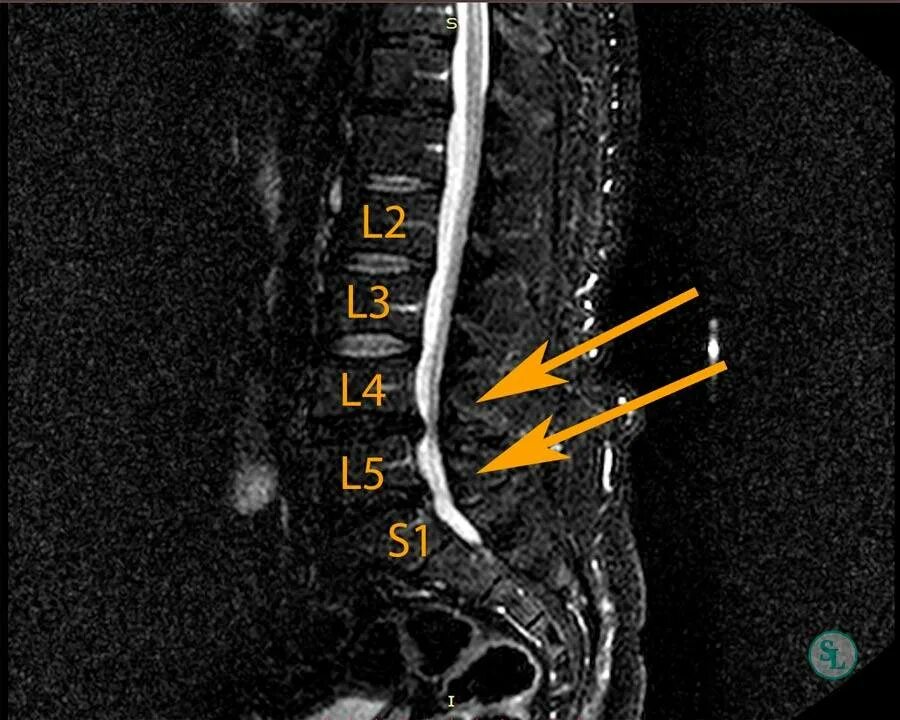

2 позвоночника